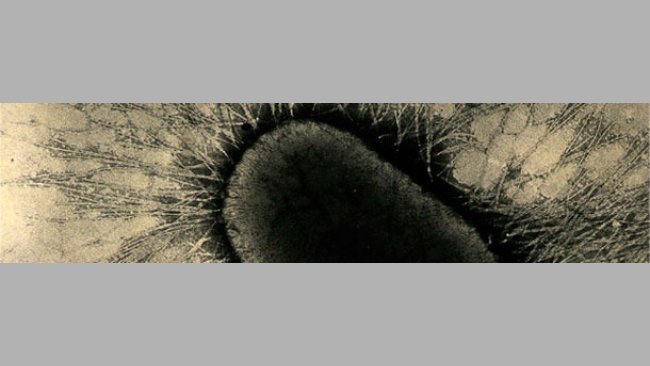

Figura 1. Cultivo puro de E. coli hemolítica em agar sangue. A zona clara em volta de cada colónia bacteriana indica hemólise (descomposição do sangue na placa de agar). Fonte: Universidade Estatal de Iowa, Laboratório de Diagnóstico Veterinário, Secção de Bacteriologia.